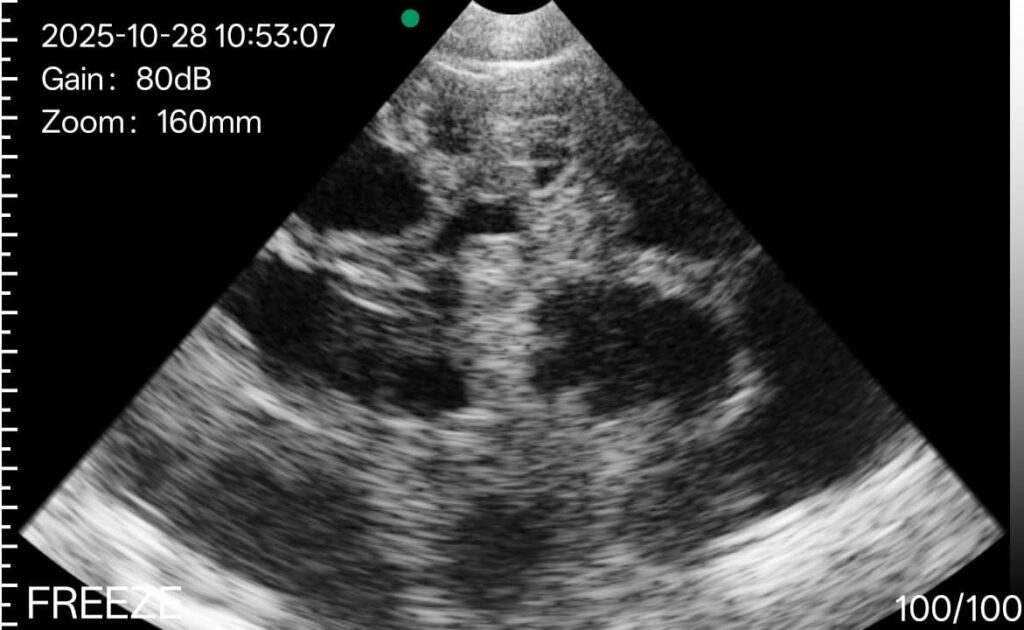

Sample of a sow pregnancy

This 28 day ultrasound image has been provided by the incredibly awesome Sean Molloy.

The triangular field of view shows the uterus filled with multiple dark, round to oval shapes. These darker areas are fluid-filled pockets that surround the developing fetuses. The lighter, speckled regions around and between them are uterine tissue and fetal structures.

The black or very dark areas represent amniotic fluid. The brighter white speckles inside or just around these dark areas are reflections from fetal bodies, placentas or membranes. Pregnant uterus will usually look busy or “structured” like this, not uniform or empty.

Not displayed above: if the black spot is very smooth around the edges this could be a sign for an ovarian cyst. Keep an eye out!